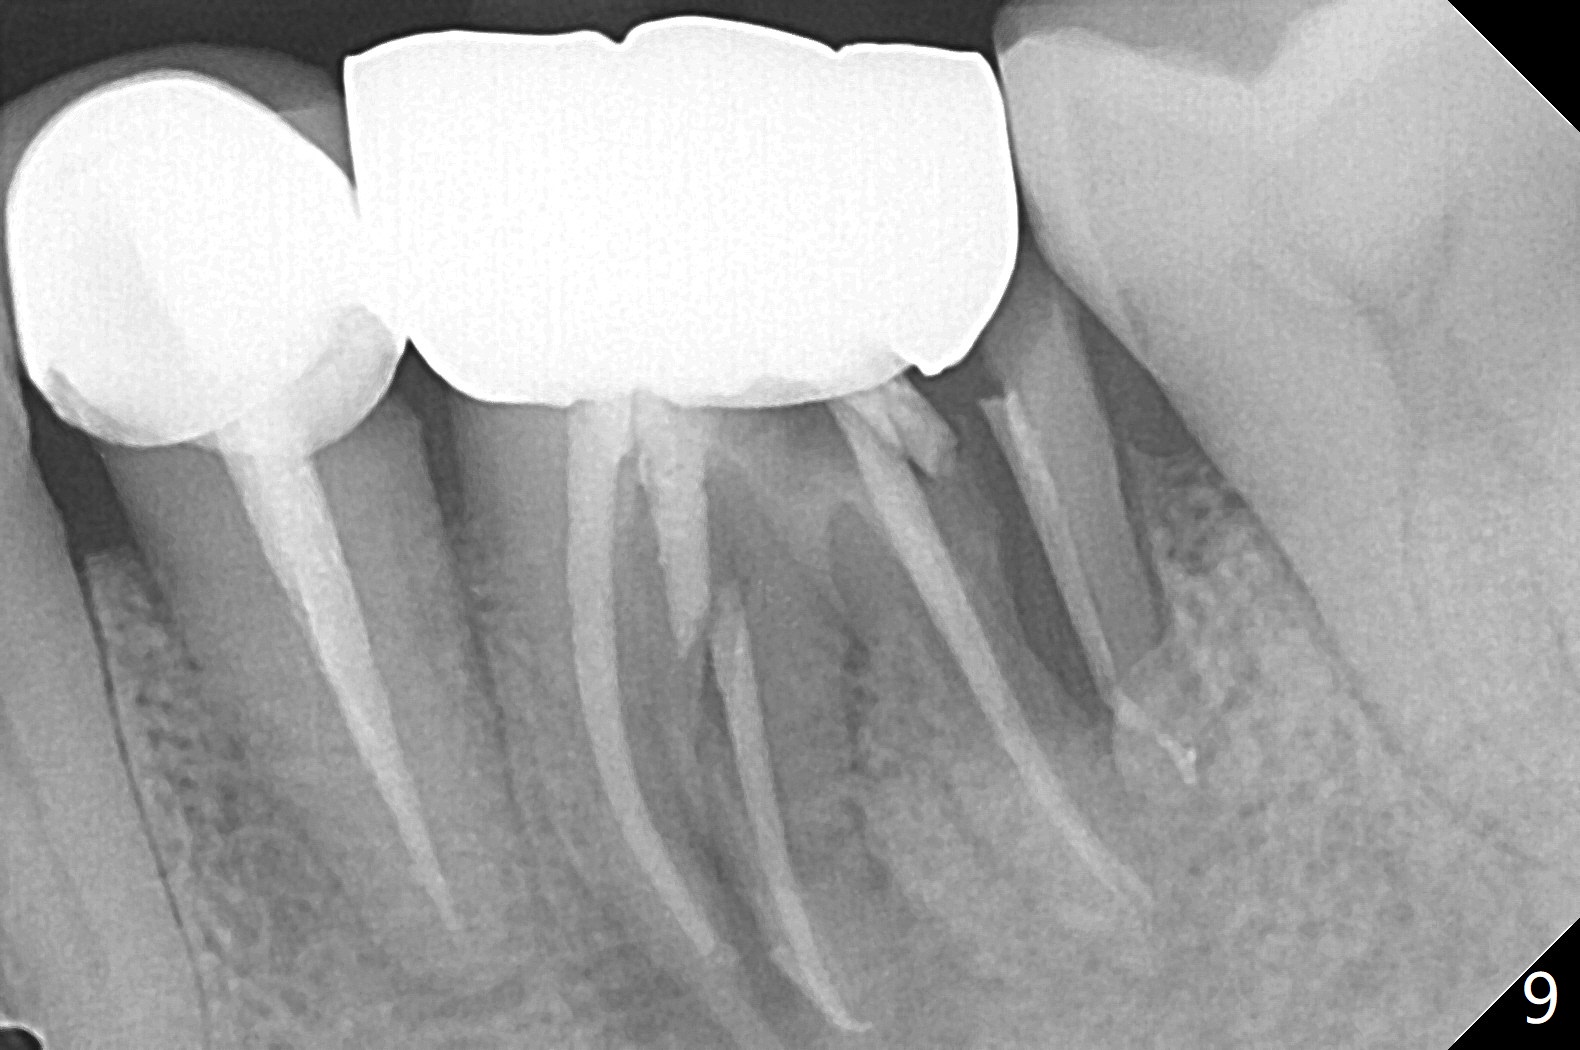

Distal Root Fracture

A 54-year-old man has distal (D) root fracture at #19 while the implant at #2 is osteointegrarting (Fig.1,2). Because of the large distal defect (Fig.3, after extraction), osteotomy (red line) will be initiated in the mesial socket (Fig.4, as distal as possible, with the coronal end in the middle of the socket) or the mesial slope of the septum (Fig.5) so that the implant (green) will be supported by the distally displaced septum (Fig.6 arrow). CT taken 8 months later confirms distal root fracture. A 6x11.5 mm or longer implant seems to be appropriate for the site (Fig.7). Three years later there is severe buccal swelling (Fig.8) with vertical mesial and distal root fractures (Fig.9). Although the buccal plate is lost, the septum remains (Fig.10 S), which will provide with blood supply to the bone graft (Fig.11), covered with Bioxclude and 6-month membrane and PSA suture. The bone density in the mesial and distal sockets is higher than that in the septum 8 months post cortical bone graft (Fig.12). In spite of bone graft, the buccolingual width reduces by almost 4 mm 8 months post extraction (Fig.3,4). In spite of bone graft, the buccolingual width reduces by almost 4 mm in 8 months post extraction (Fig.3,4). A 5x11.5 mm implant will be placed (Fig.15).